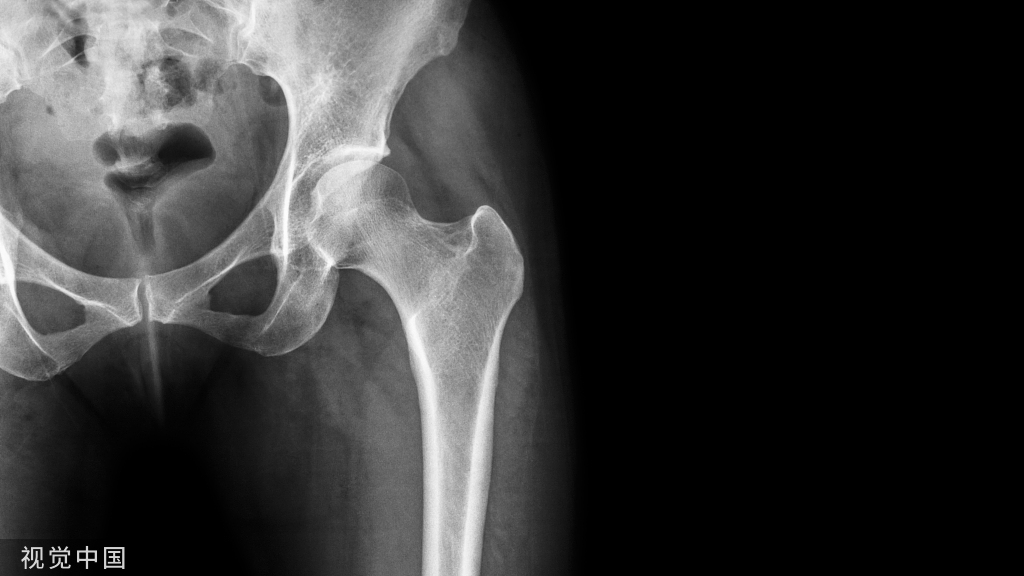

股骨近端骨折

股骨颈骨折常发生在老年人,头下型骨折最常见,但是当股骨外旋或有明显的关节炎骨赘形成时,骨折较难发现。此外,肥胖和骨量减少增加髋部 X 片诊断难度,所以需格外注意。

因骨结构重叠影响,股骨转子骨折发生轻度移位时亦很难发现,加做一个不同角度的 X 线片有助于诊断(图 7)。